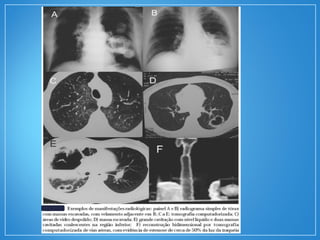

• Achados radiológicos mais freqüentes: infiltradosinfiltrados

pulmonarespulmonares (67%) e nódulosnódulos (58%), estes geralmente

múltiplos, bilaterais e cavitação em cerca de 50% dos

casos.

• A tomografia computadorizada de tórax é superior ao

radiograma simples.

• NódulosNódulos são identificados em até 70% dos casos,

variando de poucos milímetros a 10cm. Tendem a ser

múltiplos, com distribuição homogênea bilateral, e

podem aumentar em tamanho e número com a

progressão da doença.

• Cavitação é vista na maioria dos nódulos com mais de

2cm de diâmetro.

• Áreas de consolidaçãoconsolidação e vidro foscovidro fosco em diversos

padrões, entre eles consolidação com distribuição

peribrônquica, consolidação focal sem ou com cavitação,

bandas parenquimatosas, áreas de consolidação

periférica mimetizando infartos pulmonares, e áreas de

vidro fosco difusas e bilaterais, em geral representando

hemorragia alveolar.

• Manifestações menos freqüentes incluem derrame

pleural, presença de massas mediastinais e aumento de

linfonodos, em geral em associação com infiltrados

parenquimatosos.

• Achados radiológicosmais freqüentes: infiltradosinfiltrados pulmonarespulmonares (67%) e nódulosnódulos (58%), estes geralmente múltiplos, bilaterais e cavitação em cerca de 50% dos casos. • A tomografia computadorizada de tórax é superior ao radiograma simples. • NódulosNódulos são identificados em até 70% dos casos, variando de poucos milímetros a 10cm. Tendem a ser múltiplos, com distribuição homogênea bilateral, e podem aumentar em tamanho e número com a progressão da doença. • Cavitação é vista na maioria dos nódulos com mais de 2cm de diâmetro.

• Áreas deconsolidaçãoconsolidação e vidro foscovidro fosco em diversos padrões, entre eles consolidação com distribuição peribrônquica, consolidação focal sem ou com cavitação, bandas parenquimatosas, áreas de consolidação periférica mimetizando infartos pulmonares, e áreas de vidro fosco difusas e bilaterais, em geral representando hemorragia alveolar. • Manifestações menos freqüentes incluem derrame pleural, presença de massas mediastinais e aumento de linfonodos, em geral em associação com infiltrados parenquimatosos.